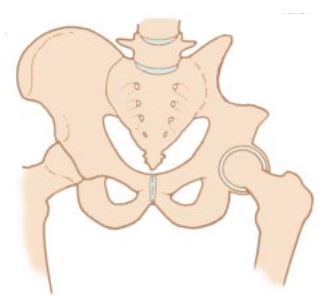

Removal of tumor and reconstruction. Once the tumor is removed the bone and joint are restored (reconstructed) if the tumor involved the “ball and socket” region. A “cup” may be utilized to replace the acetabulum if it was removed during surgery.